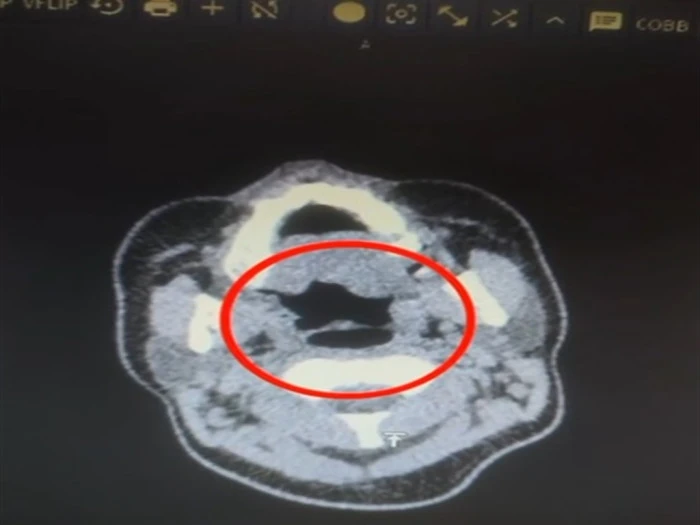

İl Emniyet Müdürlüğü Narkotik Suçlarla Mücadele Şube Müdürlüğü ekipleri, ‘Uluslararası uyuşturucu madde ticareti’ yapan kuryelerin yakalanmasına yönelik çalışma başlattı. Bu kapsamda düzenlenen operasyonda A.R. isimli kadın yakalandı. Gözaltına alınan şüpheli muayene için Kayseri Şehir Hastanesi'ne getirildi. Röntgen ve ultrasonda, A.R.’nin midesinde uyuşturucu madde olduğu tespit edildi. Şüphelinin midesinden kapsül halinde 500 gram metamfetamin, sağlık ekibinin müdahalesiyle çıkarıldı. Taburcu edilen şüpheli, polis merkezine götürüldü. (DHA)